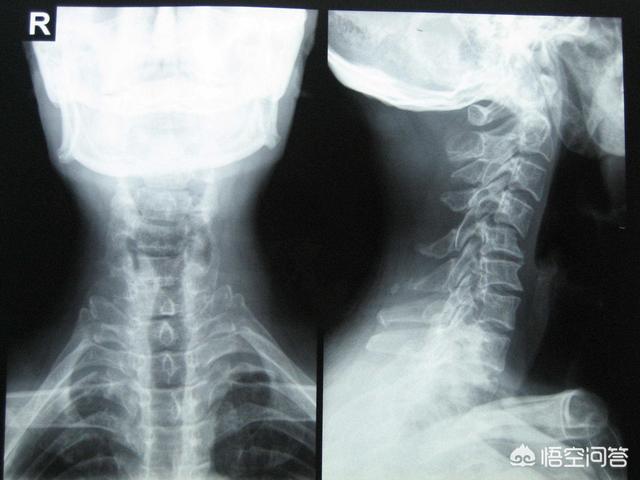

En orthopédie, il existe également des procédures plus traumatisantes, telles que l'opération de l'art orthopédique.颈椎de la chirurgie, ainsi qu'à lafracture du bassinde la chirurgie, etc.

Comme une fracture cervicale.

Ces fractures sont le plus souvent causées par des traumatismes à haute énergie, tels que les accidents de voiture, les chutes, etc. Lorsque la fracture provoque une compression de la moelle cervicale dans le canal rachidien, elle n'entraîne pas seulement une quadriplégie, mais pour les fractures situées plus haut (au-dessus de C4), elle entraîne souvent des difficultés respiratoires et affecte même les centres de circulation respiratoire car l'hématome de la moelle épinière s'étend vers le haut.

Dans ce cas, la chirurgie est risquée, mais les médecins choisissent souvent de prendre ce risque afin de maximiser les chances de sauver la vie du patient.